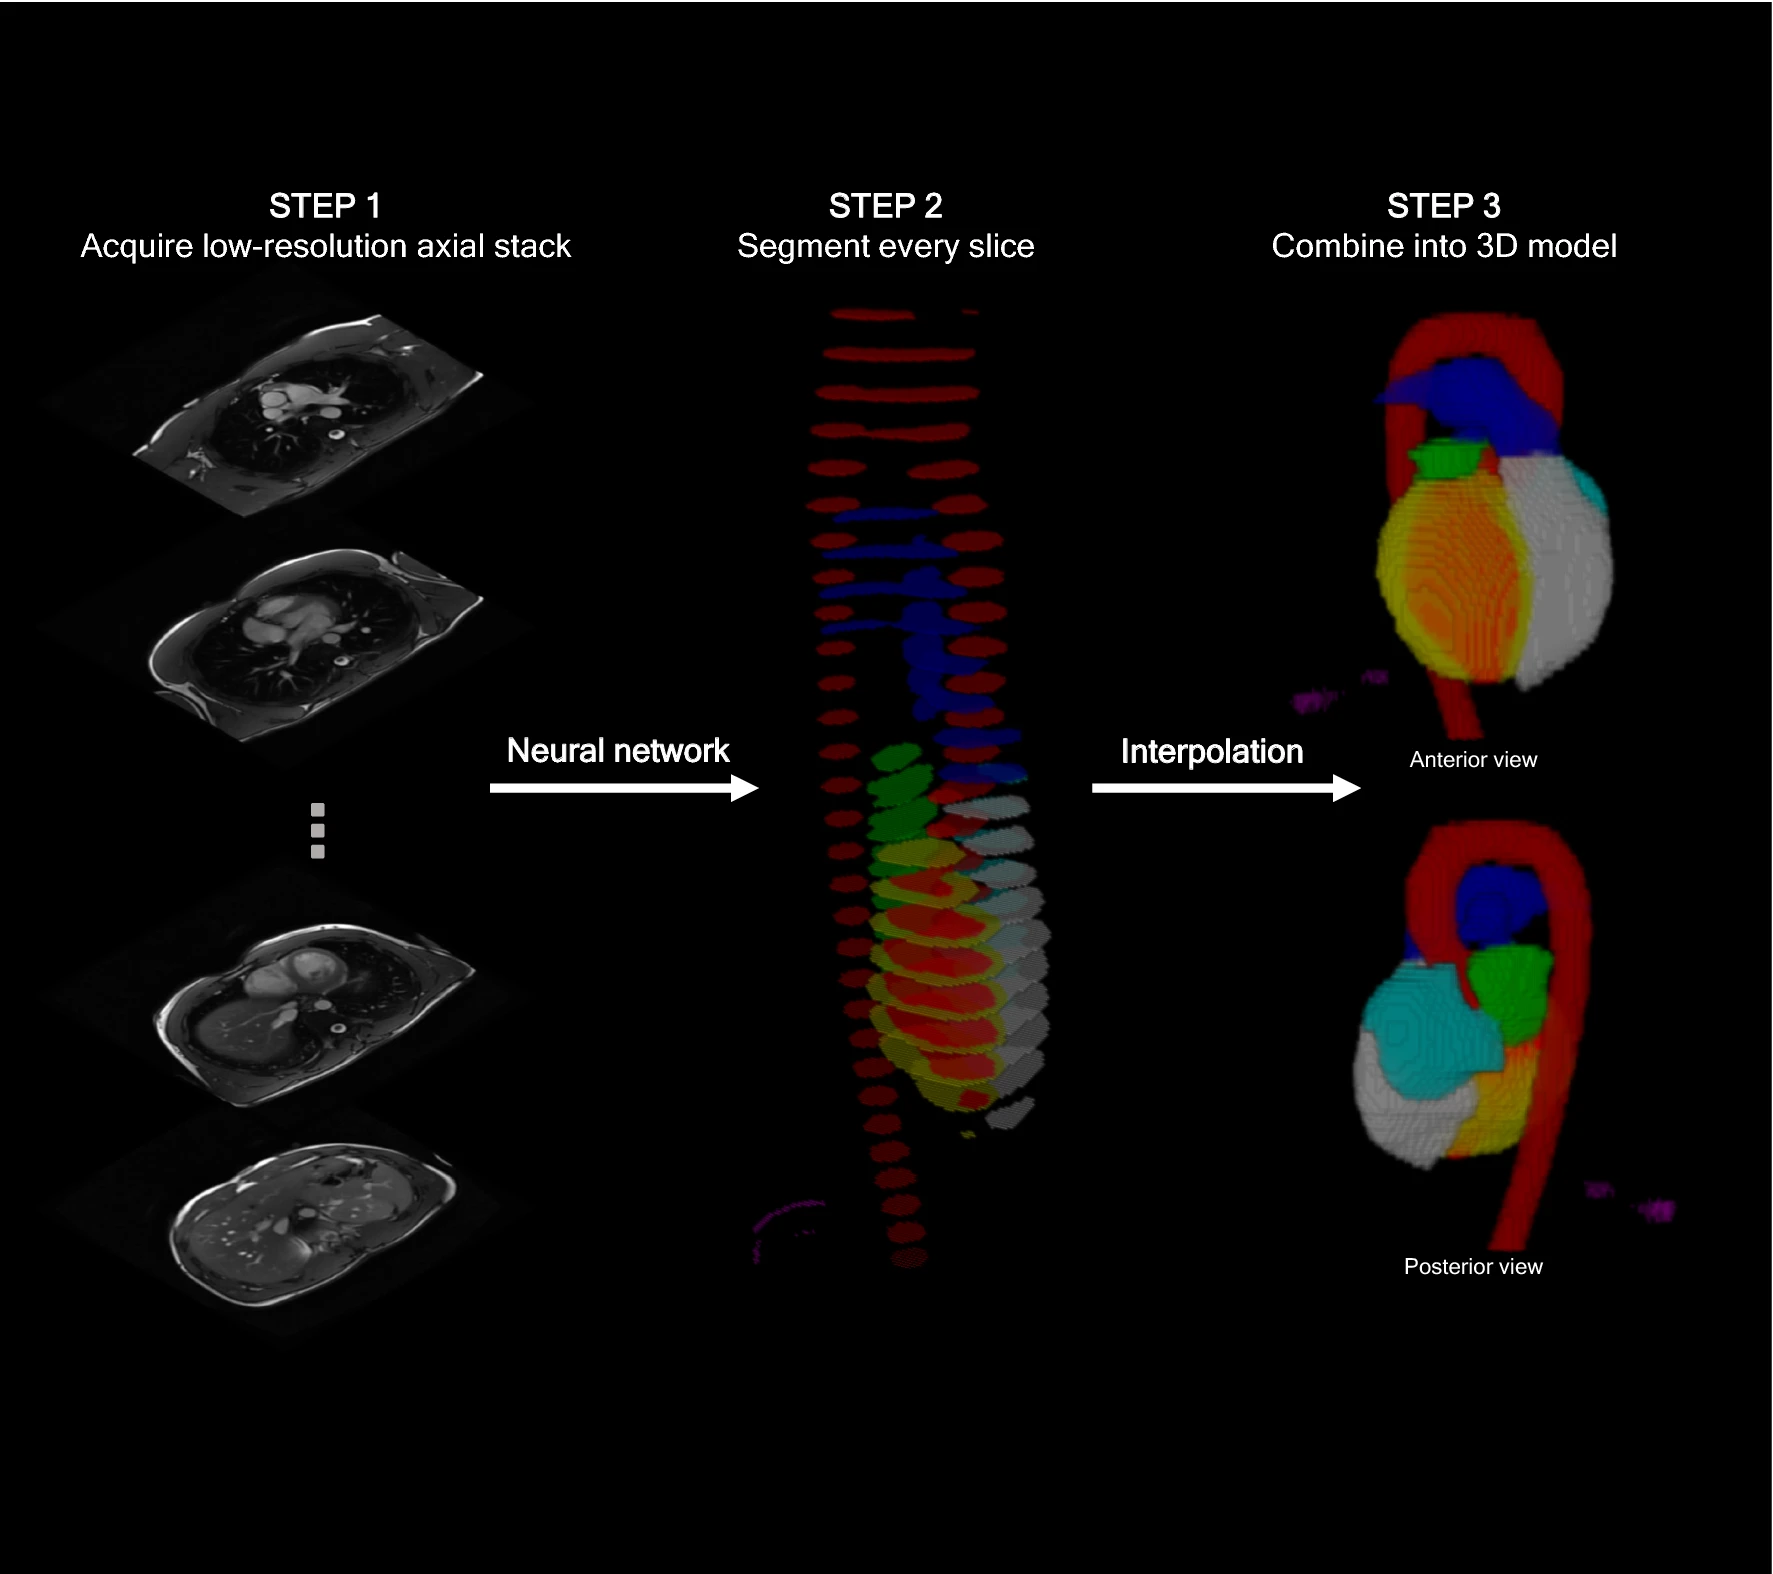

Here we use a neural network to analyse and segment each slice of these images, before combining these slices into a 3D model. This 3D model is then used to estimate common cardiac measurements made by expert humans. The hope is we can get good estimates of these measures right at the start of the scan, so any unexpected findings can be flagged up early.